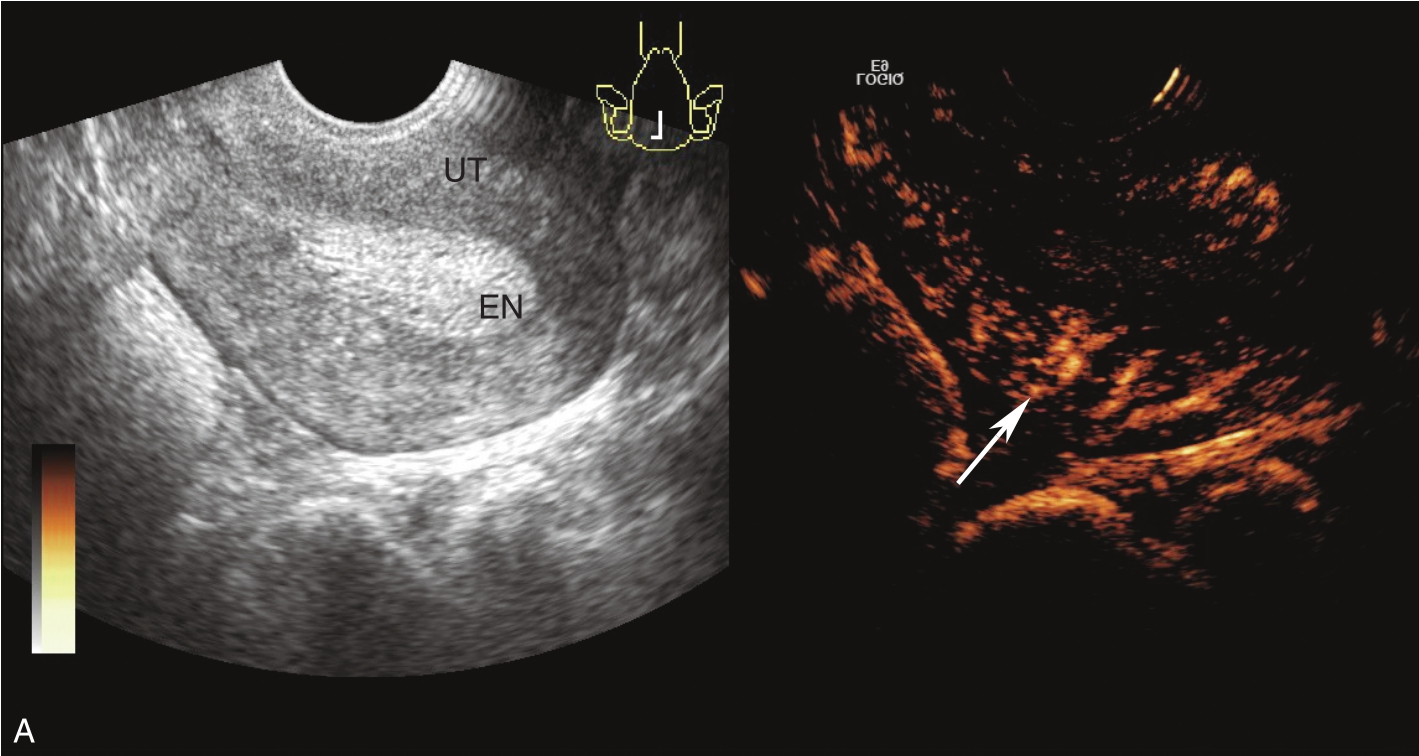

经静脉超声造影见图3-5-2及ER 3-5-1。注入造影剂后14s,子宫肌层开始增强(图3-5-2A箭头所示);子宫内膜始增时间约注入造影剂后21s,从周边开始增强(图3-5-2B箭头所示),晚于子宫肌层,向心性充填;注入造影剂后40s,内膜造影剂达峰,造影剂分布较均匀,呈等增强(图3-5-2C箭头所示);注入造影剂后73s,宫内膜晚于肌壁清退(图3-5-2D箭头所示);TIC曲线显示内膜呈晚增强、等增强、晚清退(黄色曲线代表内膜,绿色曲线代表子宫肌层)(图3-5-2E)。

图3-5-2 经静脉超声造影声像图

A.注入造影剂后14s;B.注入造影剂后21s;C.注入造影剂后40s;D.注入造影剂后73s;E.TIC曲线。UT:子宫;EN:子宫内膜;A、B、k、C:拟合曲线方程式的系数;MSE:均方误差;TtoPk:达峰时间;Area:曲线下面积;Grad:梯度;ATm:到达时间;TI:时间强度。

此病例为子宫内膜复杂性增生,其经静脉超声造影有如下特点:①增强早期,增生的子宫内膜与正常内膜增强模式类似,即晚于肌层增强。因复杂性增生无肿瘤血管,故时相无变化。②增强晚期,与正常内膜增强模式不同,晚于肌层清退。③复杂性增生可伴有小血管的增生,呈等增强,并使造影剂增强晚期清退时间延长。综上,内膜增生造影表现为“慢进慢出”均匀等增强。